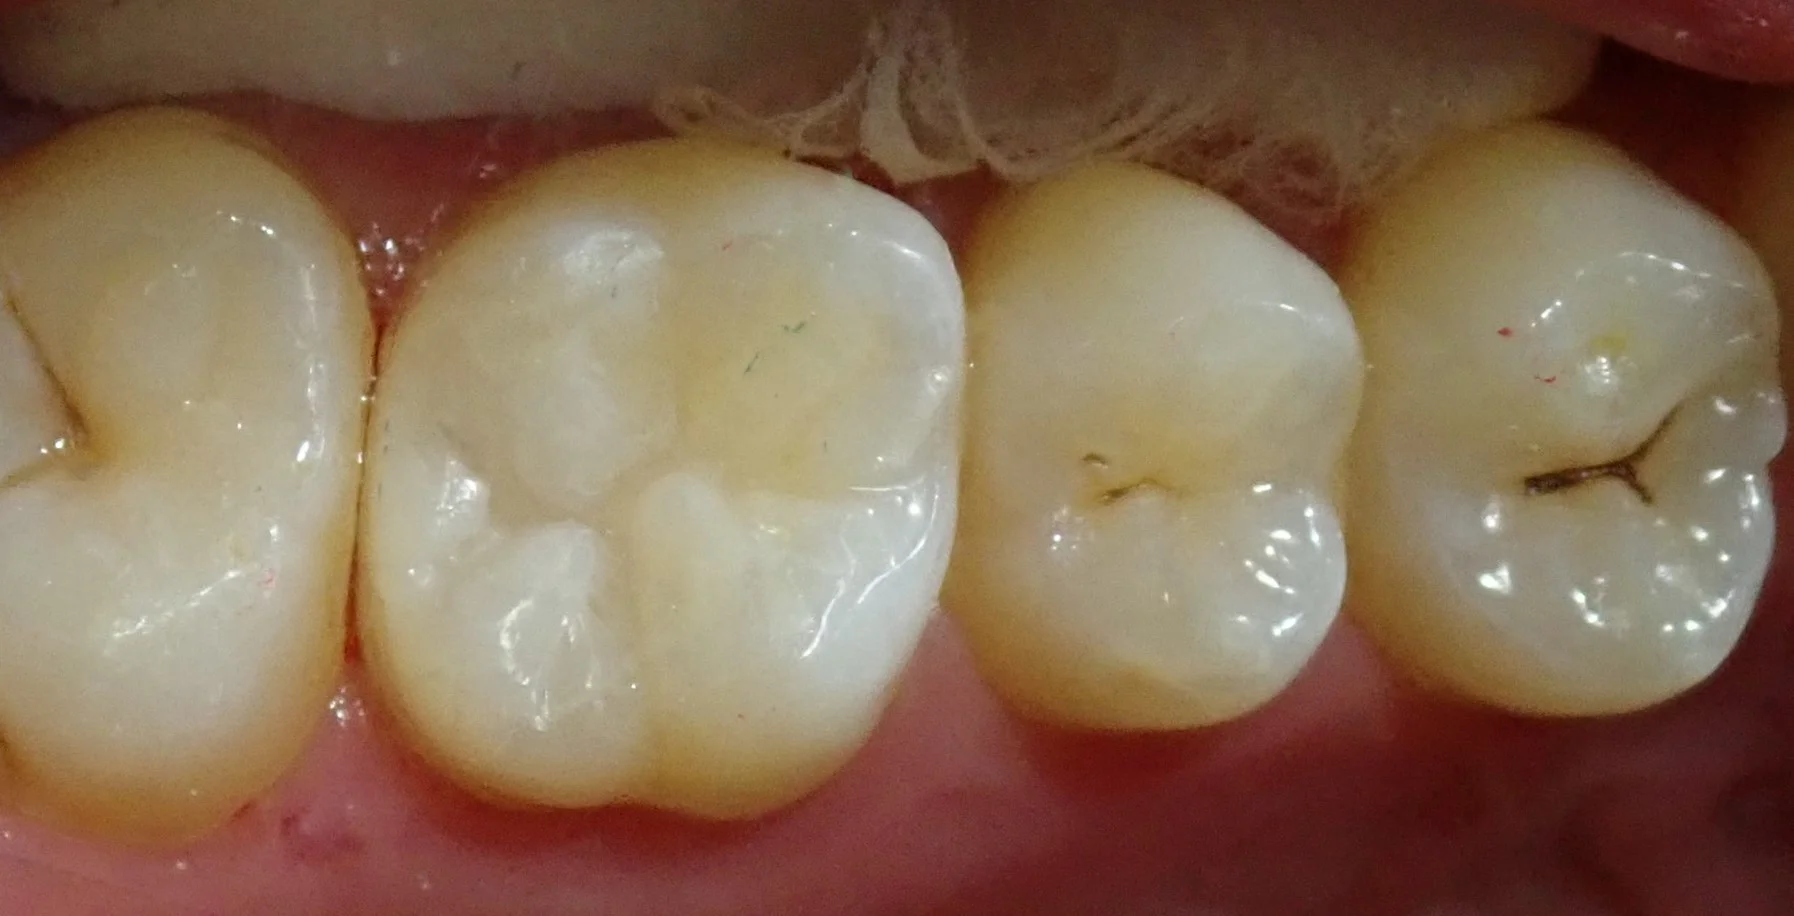

そして詰め終わったのがこちらです。

詰めるのに時間が掛かったため、歯が白く変色しており、詰めた部分が浮いているように感じるかもしれませんが、

1週間もすればこの歯の部分に水分が戻り、色は更に馴染んでくれます。

術後確認のためにフロスを通してみても、一切の段差などはなく、問題なく仕上がっていました。